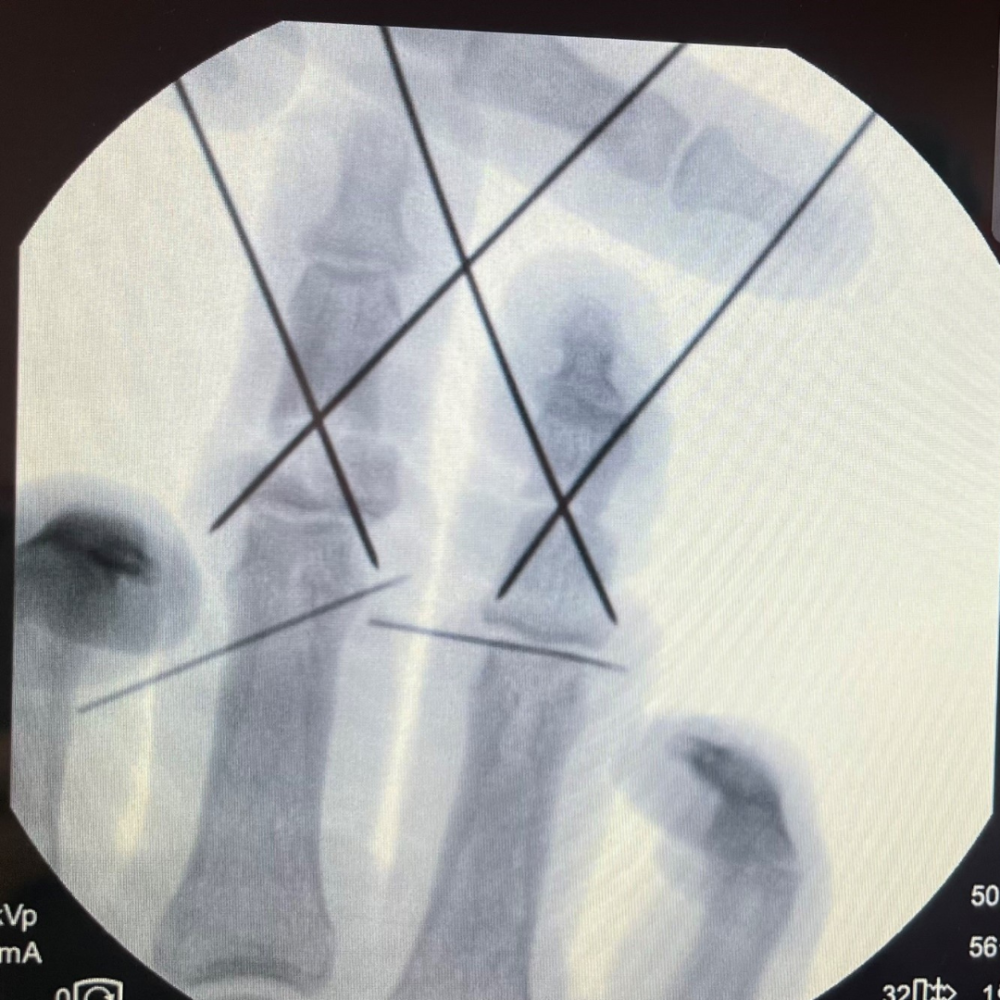

Lekarze operujący i lekarz anestezjolog przyjechali z domu, rezygnując ze swojego wolnego czasu, po to aby pomóc 22-latkowi. Uraz palców był wyjątkowo ciężki, ponieważ doszło do zmiażdżenia brzegów rany i rozległego uszkodzenia naczyń, a organizowanie zespołu zawsze trwa i zabiera ceny czas. Operacja  rozpoczęła się o północy i trwała około 8 godzin. Wymagała przeszczepów żył i skomplikowanych procedur jak płaty żylno-żylne, które wyjątkowo rzadko są potrzebne w takich sytuacjach.